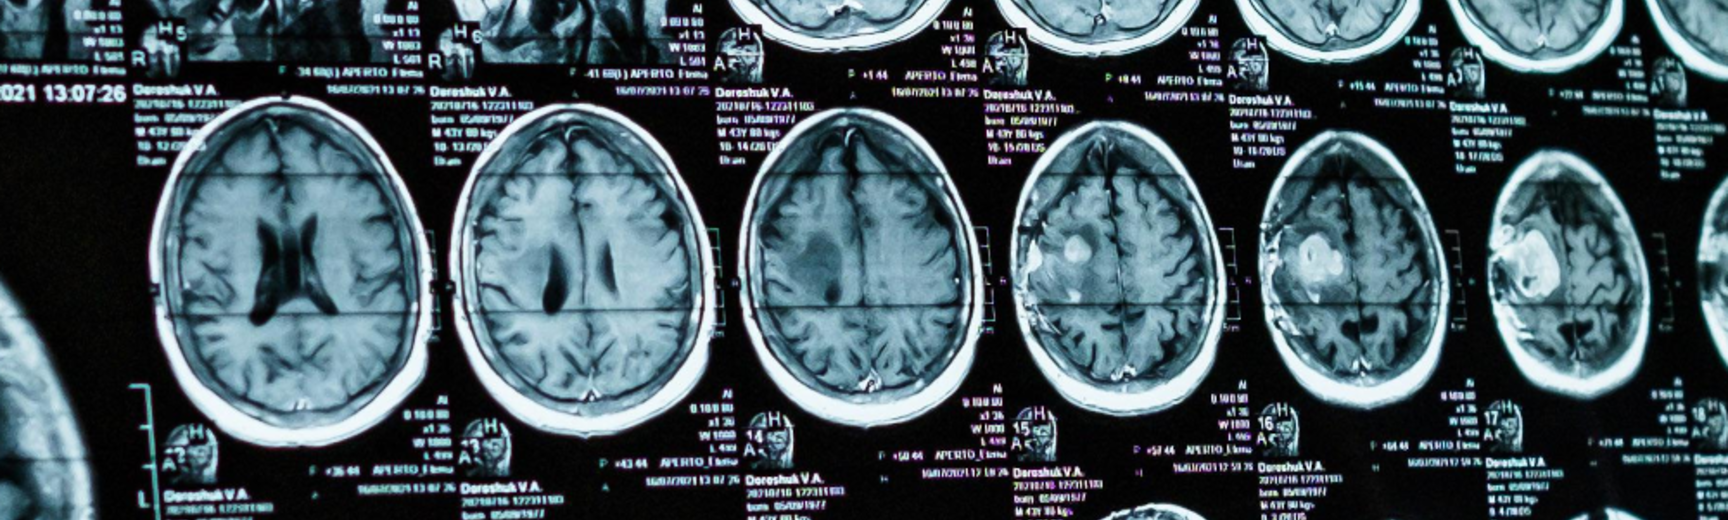

The Terri Schiavo case illustrates the heated controversy surrounding brain-damaged patients with disorders of consciousness. Some patients have suffered such severe brain damage that they have completely lost the capacity to be aware of themselves or their environment. This is known as the vegetative state. But patients with what is now known as the ‘minimally conscious state’ still possess at least rudimentary and intermittent awareness. These conditions raise difficult ethical questions. Is it in the interest of the patient to continue living in these conditions? Is it ever permissible to let such patients die rather than keep them alive at great cost? Or is life always sacred, and must never be ended, even if living is no longer a benefit to the patient? Can we be confident that awareness is really missing, and can we use neuroimaging to identify consciousness, or even communicate with seemingly non-conscious patients? If consciousness is present, but only in a rudimentary way, would this be a good thing, or rather make things worse, because only conscious patients can suffer?